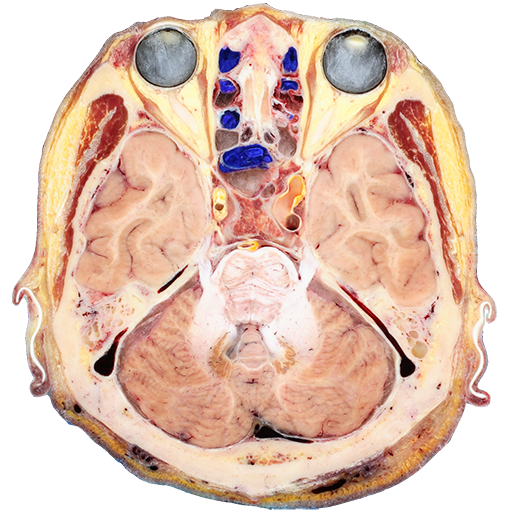

머리 단면을 실제빛깔로 낱낱이 볼 수 있는 절단면영상이 있다. 본 소프트웨어에서는 이 절단면영상을 연속으로 보거나, 확대해서 볼 수 있다. 절단면영상에서 보이는 각 구조물의 이름도 볼 수 있다. 본 소프트웨어는 절단면영상의 해상도를 줄인 버전이고, 원본 해상도의 영상을 얻고 싶으면 http://neuroanatomy.kr에서 직접 다운로드하면 된다.

소프트웨어 개발: 동국대학교 의과대학 해부학교실 (박진서, 박준형)